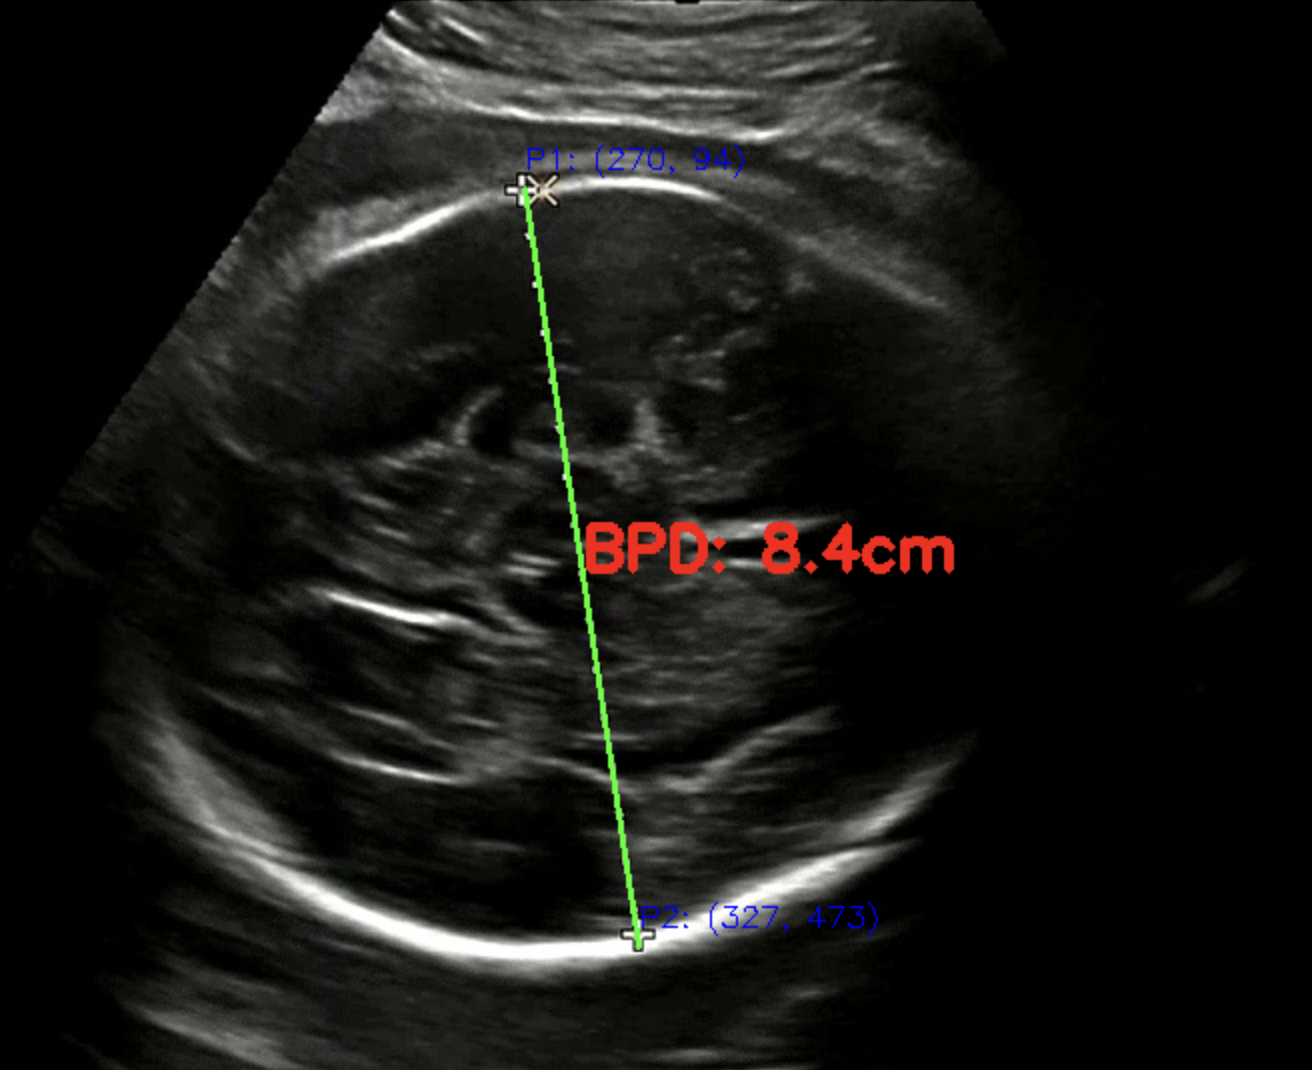

초음파 이미지 내에서 태아의 머리 가로 길이를 (이하: BPD) 계산할 때 가장 어려움을 겪었던 것은 배율 계산이었다. 안타깝게도 우리의 초음파 영상 데이터는 DICOM 파일이 아닌 단순 녹화본이기 때문에 어떤 메타데이터도 얻을 수 없는 상황이었다. 하지만 링크를 통해 배율을 얻을 수 있었다. 더 좋은 방법이 찾겠지만 현재까지 시도했던 여러 방법 중에 오차가 가장 적었다. 그리고 여러 초음파 이미지를 대상으로 테스트를 진행했는데 두개골이 제대로 인식되지 않았다. 후-우 😭

점선 패턴을 인식하는 방법을 선택했다. 점선 패턴은 BPD 를 측정할 때 모든 영상에 출력된다. 그리고 우리는 개발자이기 때문에 의사의 판단을 넘어서는 행위를 하면 안 된다고 생각했다. 그래서 점선 패턴을 인식하고 같은 선상에 있는 점들을 찾아냈다. 그리고 찾아낸 점들 중 가장 먼 좌표 간 거리를 계산하여 픽셀 거리를 획득했다.